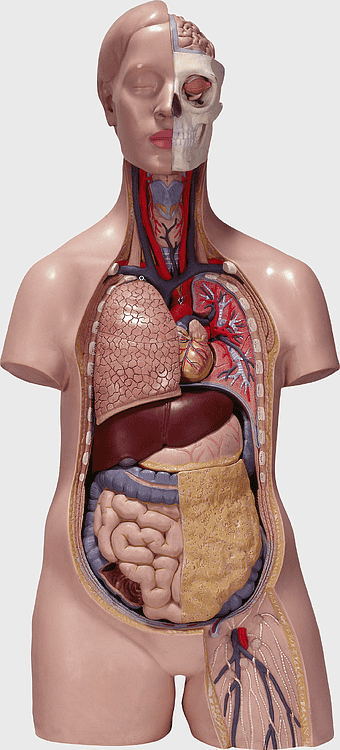

female human organ model, human digestive system anatomy, gastrointestinal tract illustration, liver and stomach diagram, medical education visuals, anatomical study aids, human body internal structures -

human anatomy diagram, esophagus and stomach model, connective tissue structure, Homo sapiens internal organs, human digestive system illustration, anatomical mannequin cross-section, skeletal and muscular system display -